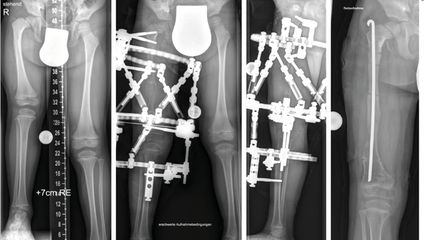

Korrektur assoziierter Gelenkspathologien beim kongenitalen Femurdefekt

Der kongenitale Femurdefekt ist eine der spannendsten und komplexesten angeborenen Fehlbildungen in der Kinderorthopädie und in der klinischen Präsentation sehr vielgestaltig. Während ...